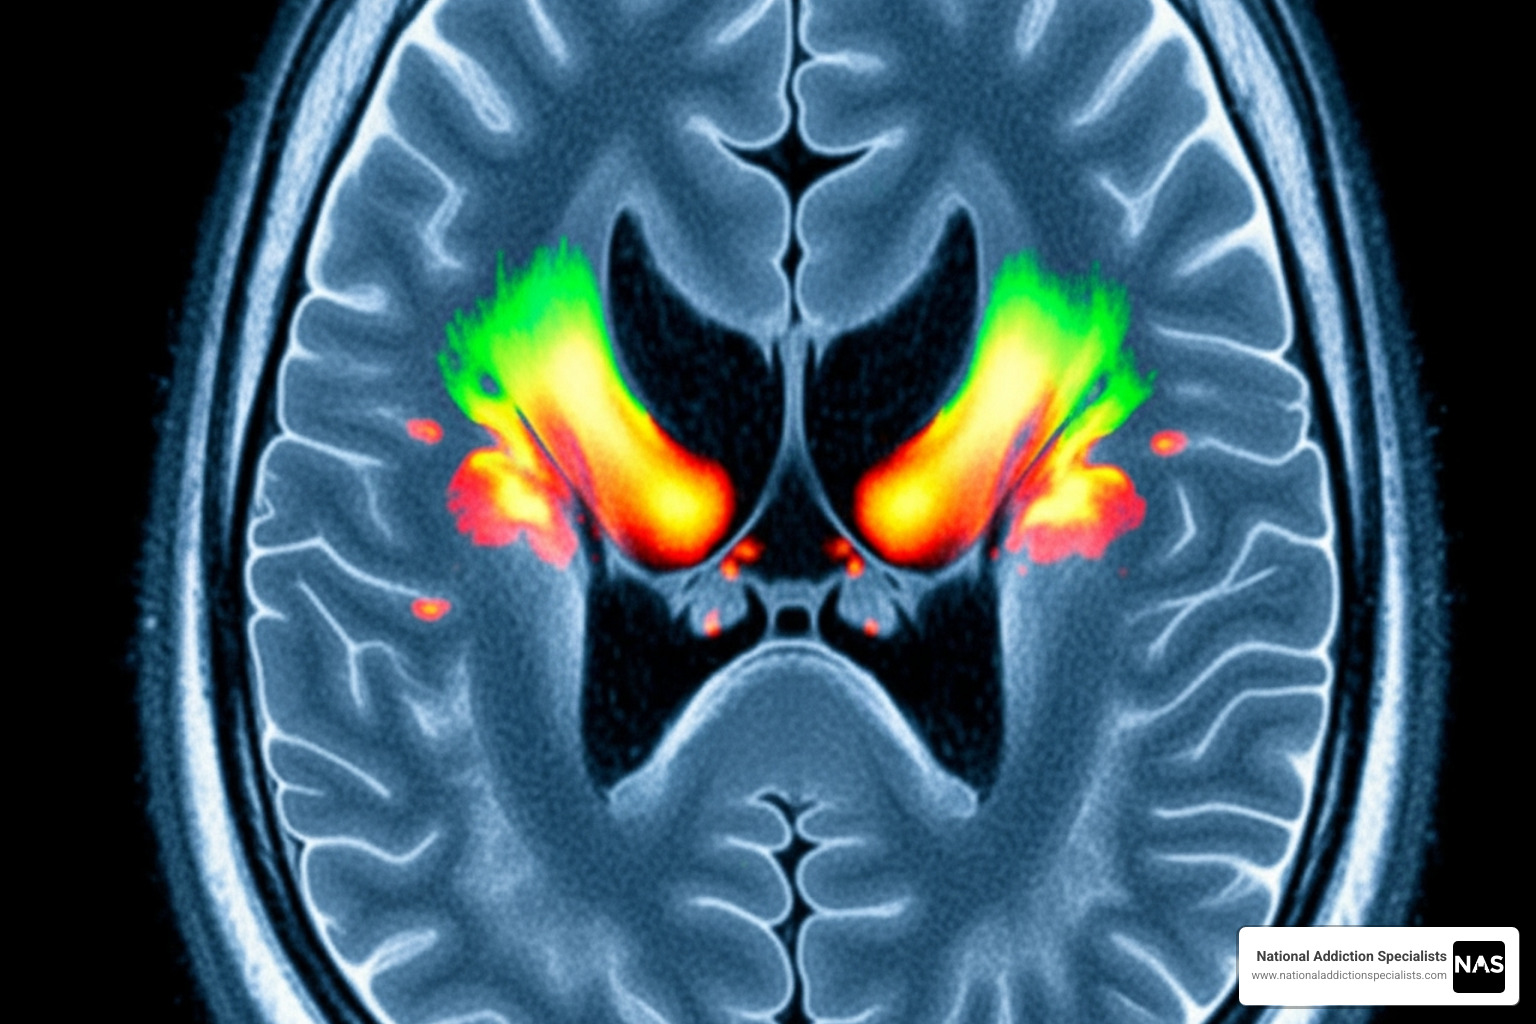

Before exploring the path to recovery from opioid addiction, it’s important to understand that Opioid Use Disorder (OUD) is a chronic medical condition that changes how the brain works, not a character flaw.

Opioids hijack the brain’s reward system by flooding it with dopamine, creating an intense high. The brain adapts by producing less natural dopamine, leading to a need for more opioids just to feel normal. This is biology, not a moral failing. Physical dependence occurs when the body adapts to the drug, causing withdrawal if stopped. Addiction is different, involving compulsive drug use despite negative consequences, driven by lasting brain changes.